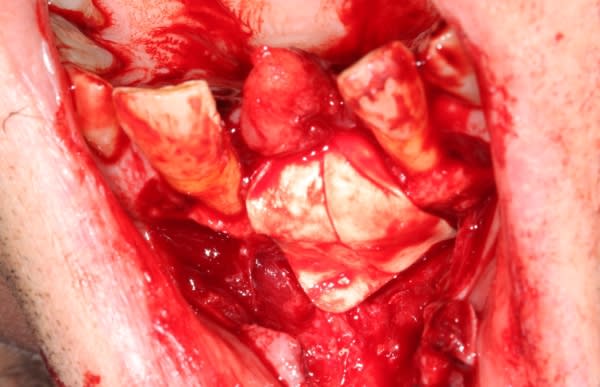

Extraction implantation immédiate mais il y a au moins 7 spires à nue... (photo 1, 2)

dans cette technique un pilier de 2mm de haut est vissé sur l'implant, ce pilier contient un orifice qui permet de transfixer la barre (photo 3,4)

l'espace créé est rempli avec un biomat et le tout est recouvert d'une membrane

la suite 6 mois plus tard

photo 3 reconstruction avec le pilier en place

photo 4 vue occlusale de l'implant et de la reconstruction osseuse obtenue